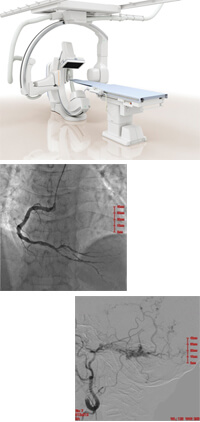

血管撮影検査

平成27年4月に血管撮影装置を導入致しました。 カテーテルという細い管を血管内に挿入し、そこから造影剤を注入することにより全身の血管を連続的に撮影する装置です。 当院では、循環器領域の血管内治療(PCI)を行うためにバイプレーン装置(一度に正面と側面の2方向からの撮影が可能)を導入致しました。 これらの装置は新しいX線検出器である「フラットパネルディテクタ」と最新の画像処理技術により、従来よりも検査時間の短縮、造影剤の使用量や放射線被曝量を少なくし、高精細な画像が撮影可能です。

また、細くなった血管を拡張したり、未破裂の動脈瘤ではプラチナコイルを挿入し、動脈瘤内で凝血塊を形成させて破裂を未然に予防したり、肝臓癌などでは血管を塞栓、閉塞させることにより出血や腫瘍に対する治療を行ったりと、検査と同時に治療(血管内手術)も行っています。

また、全身広範囲をカバーすることが可能なマルチアクセスタイプのCアームシステムを採用しており、心血管治療だけではなく、下肢血管・腎動脈など、患者さんの全身血行状態の改善が行えます。